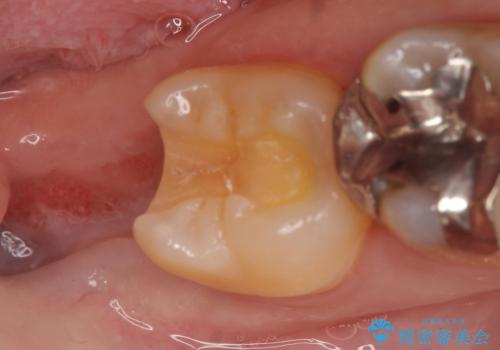

- 右下奥歯がたまにしみるので診て欲しいといらっしゃった方の症例です。

右下7番目の歯の歯茎より深い位置に虫歯があったため、親知らずを抜歯後PGA(ゴールド)インレーによる修復を行いました。